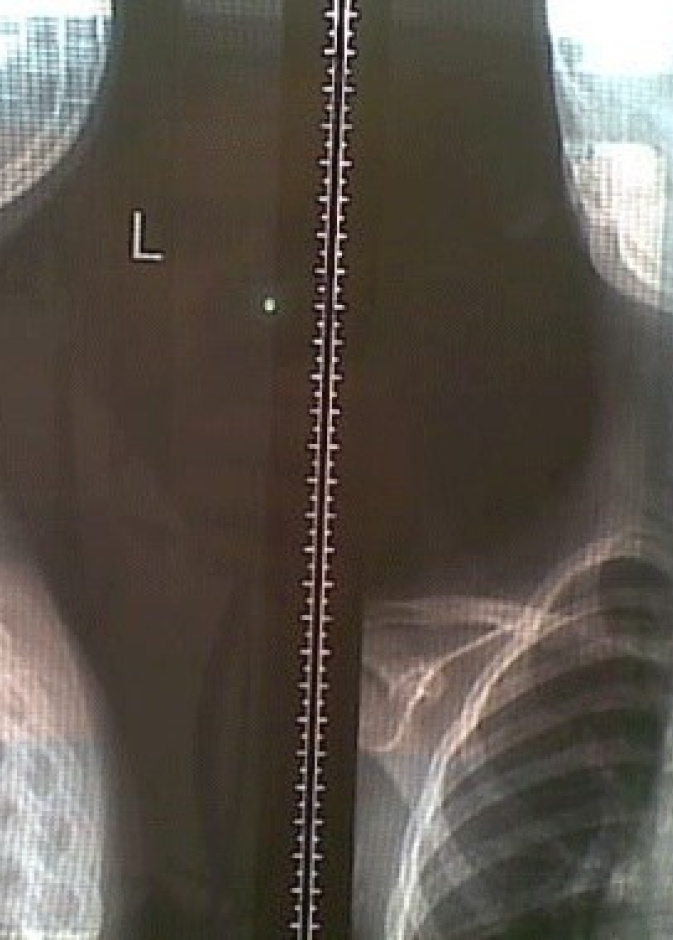

يستكشف الأطفال العالم من حولهم من خلال تحسس الأشياء ووضعها في الفم، ونتيجة لهذا يمكن أن يبتلع الكثير من الأطفال أجساماً غريبة متنوعة الشكل والحجم، ويقع الأهل…